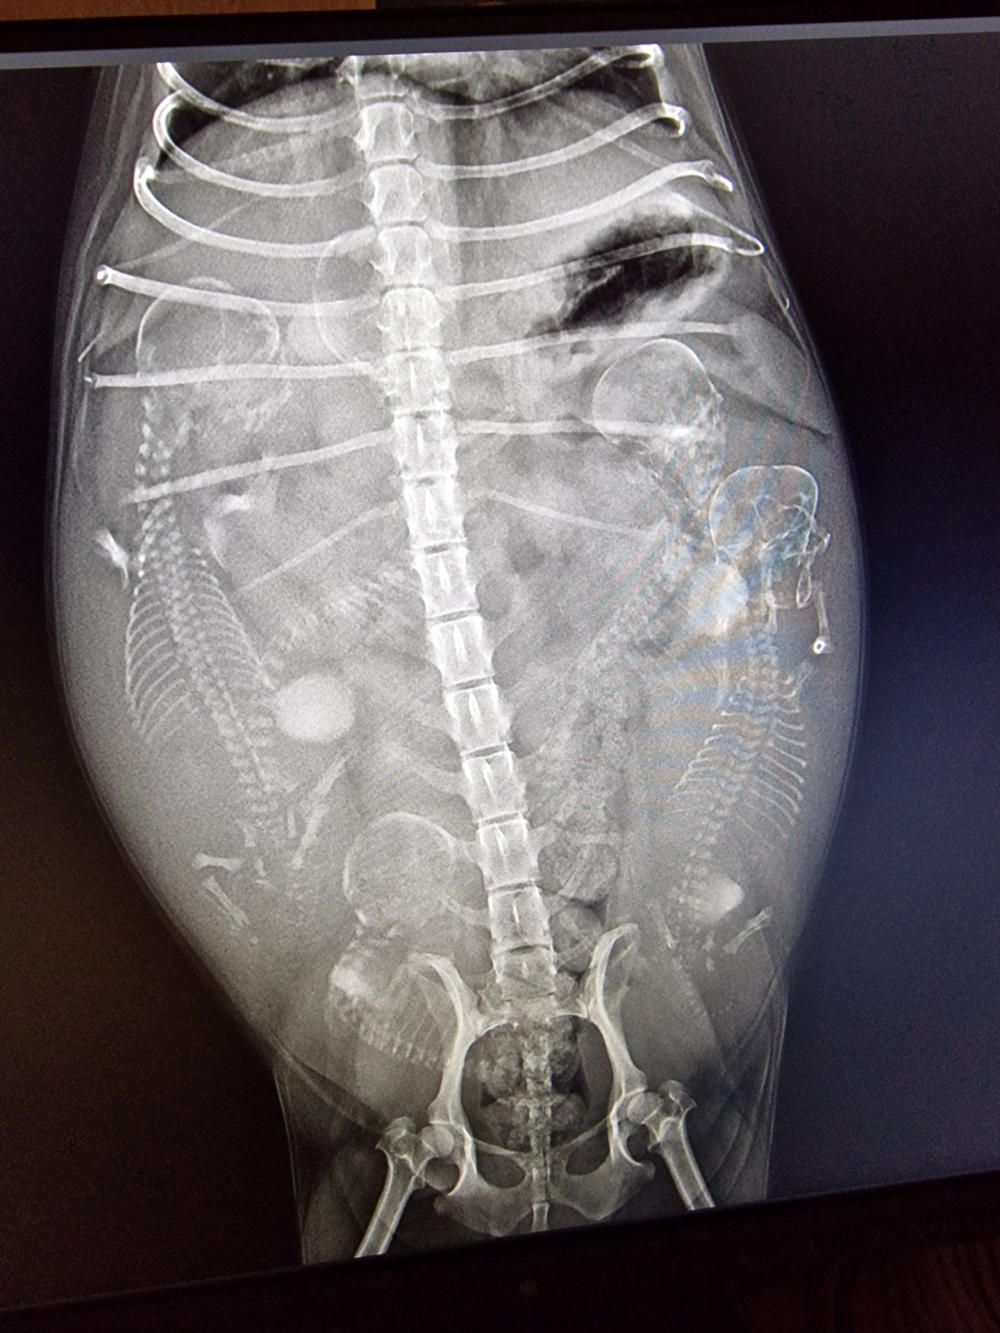

Gestern hat unsere Mona ihr Baby zur Welt gebracht. Ihr wundert euch sicher, dass wir nix gesagt

haben. Aber wir waren schon „etwas geschockt“, als unser Frauli gemeinsam mit der TÄ nur eine

Fruchtanlage auf dem Ultraschallbild gesehen hat. Deshalb dachten wir uns, warten wir mal das

Röntgenbild ab. Aber auch das zeigte keinen weiteren Welpen und der eine sah zudem auch noch

sehr groß aus und er lag quer. Deshalb haben wir das nicht „an die große Glocke gehängt“, sondern

wollten erstmal abwarten, bis der Zwerg gesund auf der Welt ist. Und das hat Mona zum Glück

gestern Abend „geschafft“. Näheres jetzt unter P1-Wurf.